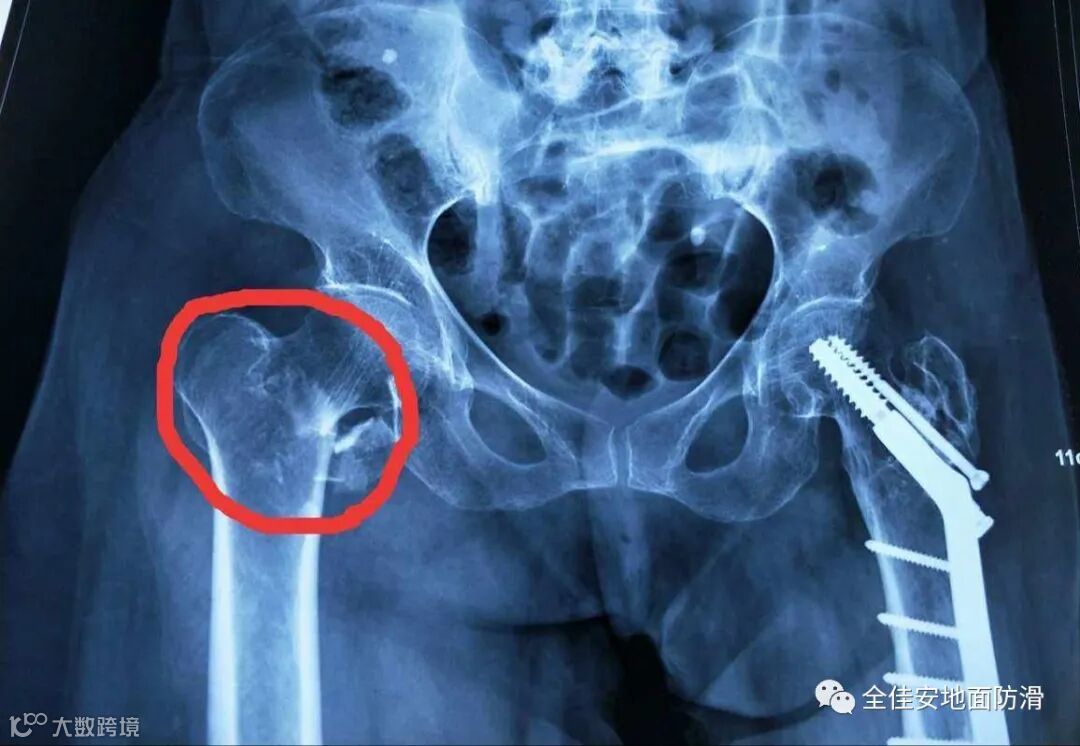

在晚上6点左右,王某在坐下起身时臀部处疼痛难忍,饭后在其丈夫护送下前往附近医院就诊,经医院诊断,此次摔倒导致王某骨折受伤。